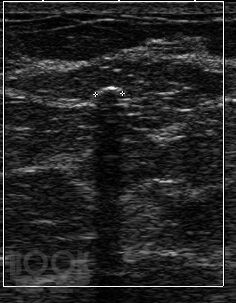

В данном пособии систематизированы сведения об артефактах, которые имеют место при выполнении ультразвуковых исследований. Отдельно рассмотрены эффекты, возникающие в режиме серой шкалы и при выполнении допплеровских исследований. Представлены разработки авторов по изучению допплеровского «мерцающего артефакта» и акустических потоков. Даны рекомендации, позволяющие уменьшить отрицательное влияние артефактов на качество диагностического изображения.